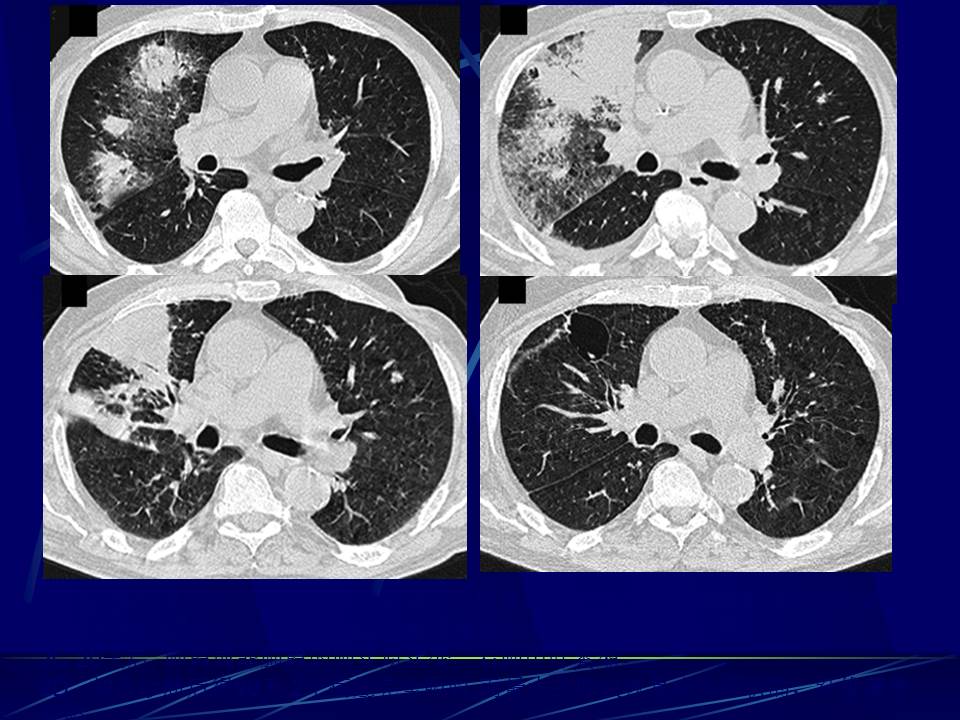

肺部真菌感染影像学分析